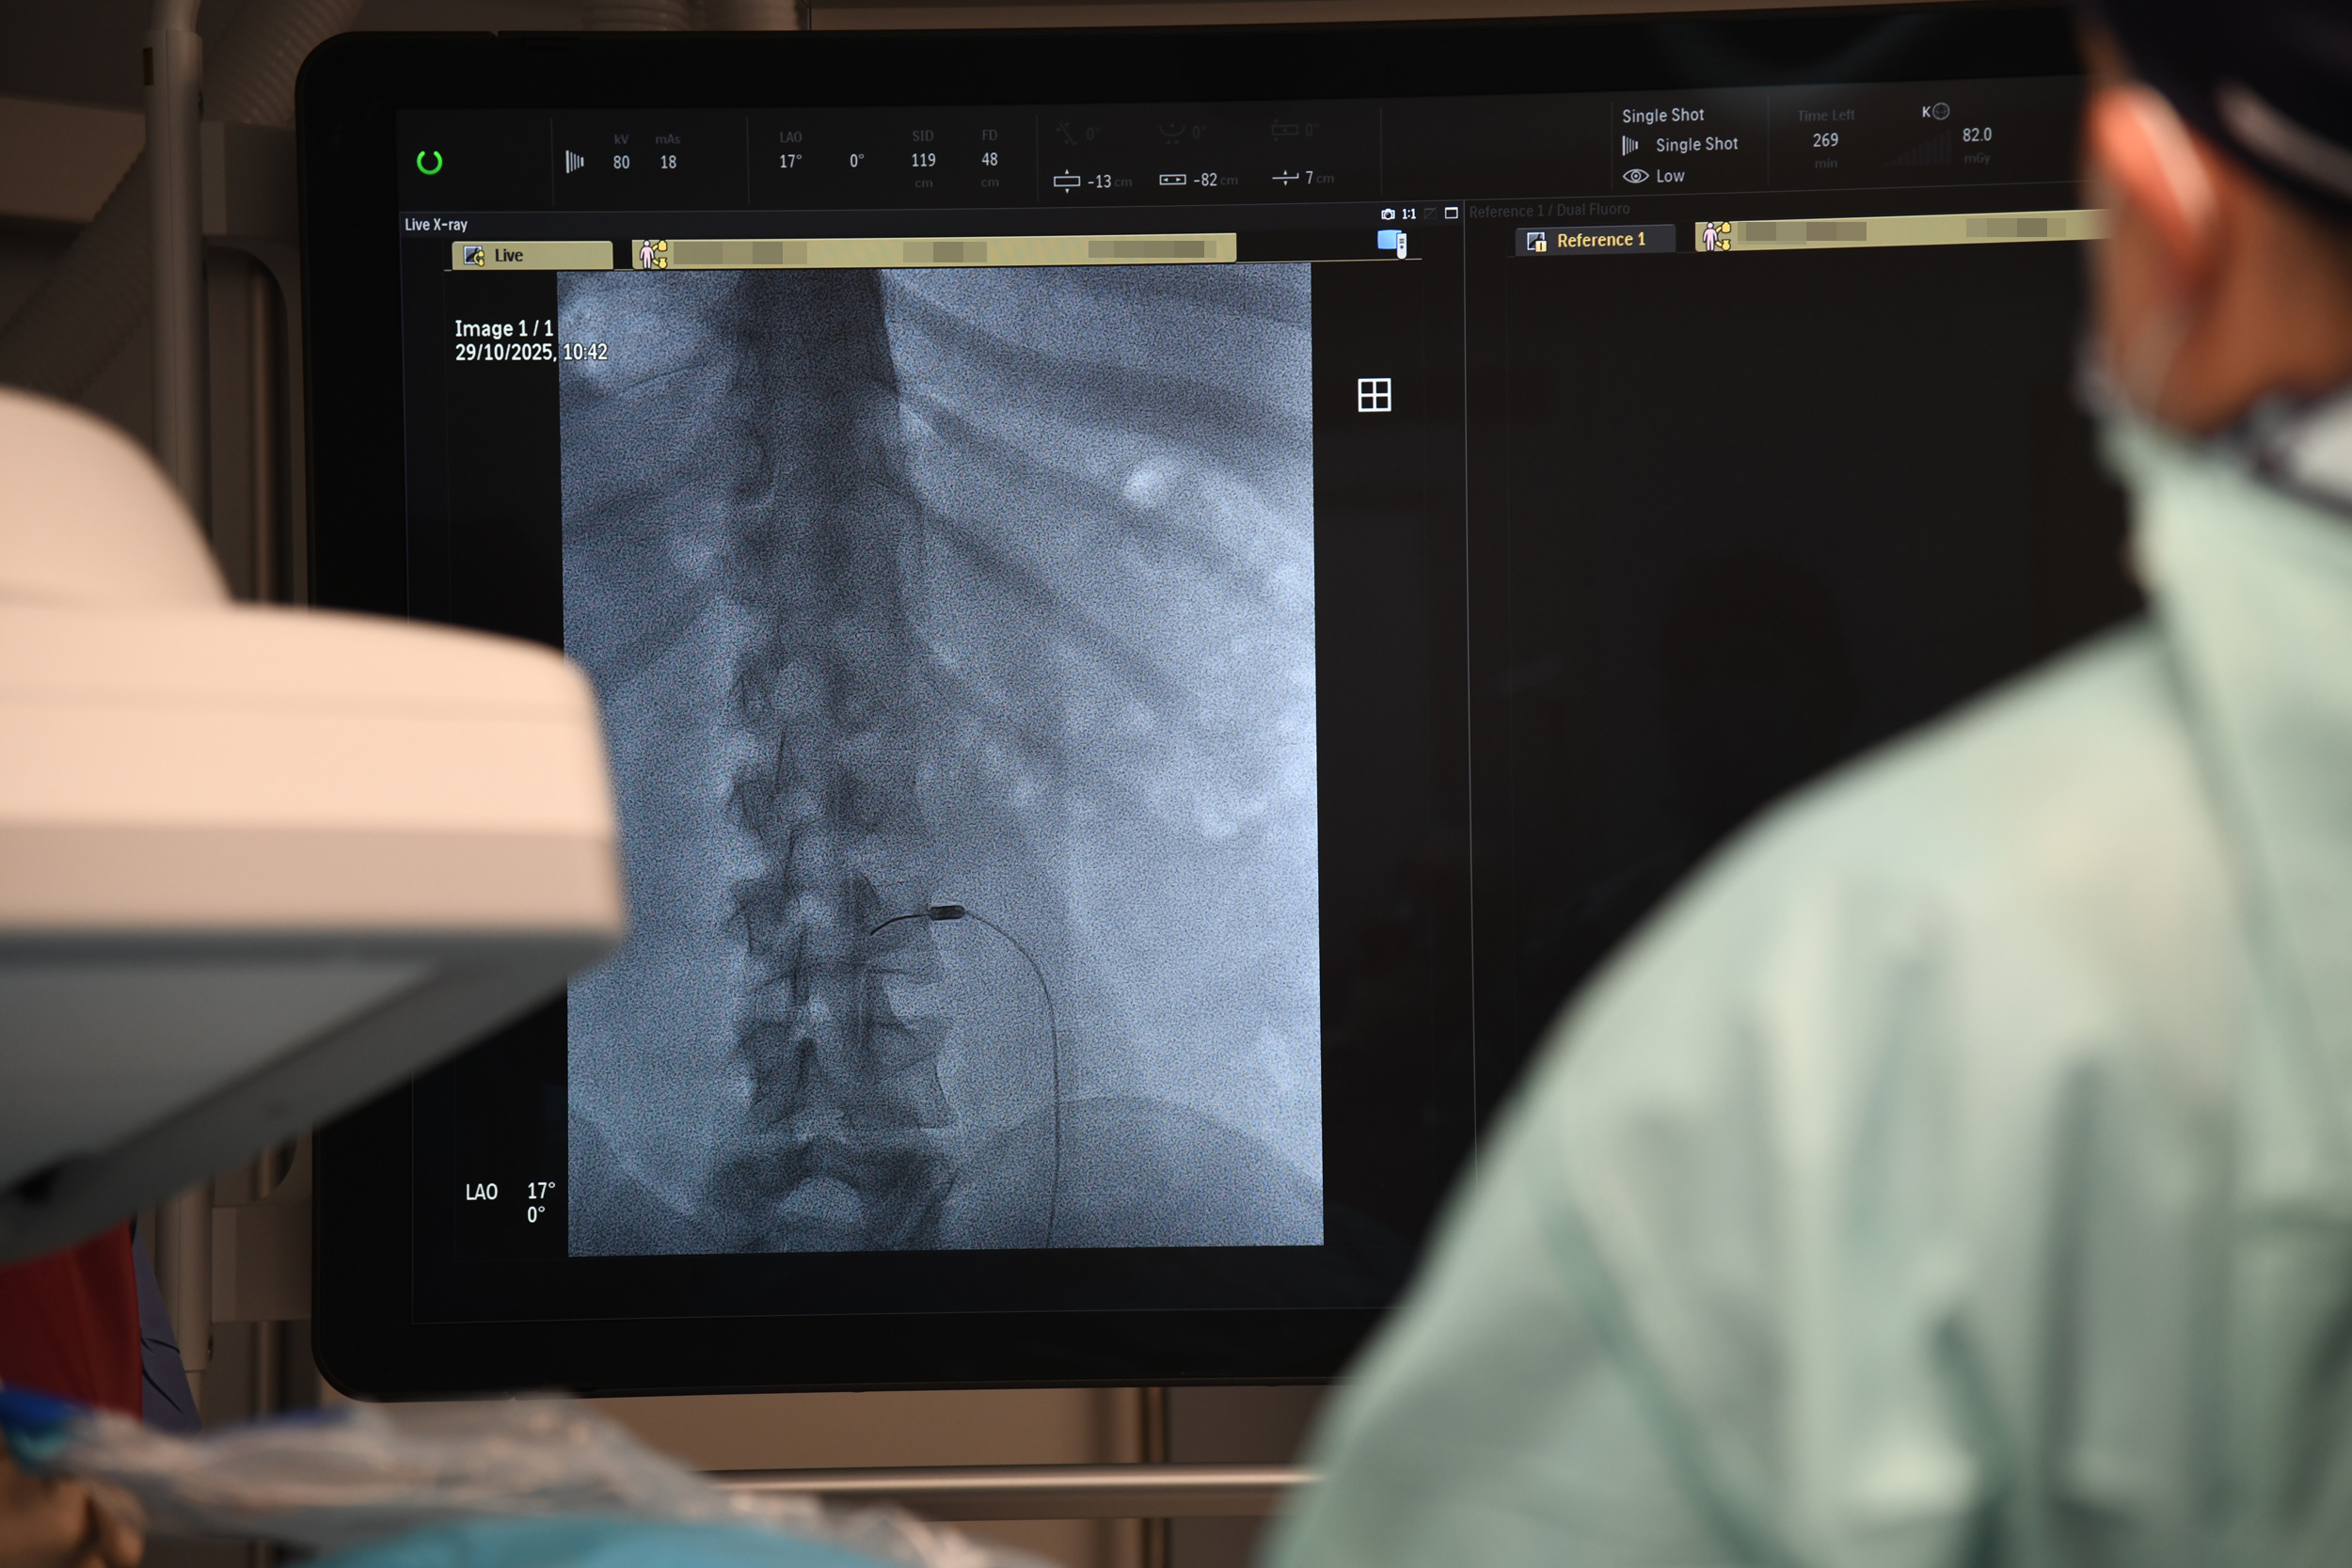

– Z przeciążenia stawów międzykręgowych. Co można wtedy zrobić? Zniszczyć unerwienie tych stawów. Robimy to wbijając igłę, pod kontrolą prześwietlenia rentgenowskiego, bo jest to metoda wymagająca precyzji. Do igły wprowadzamy emiter prądów wysokiej częstotliwości i nagrzewamy tkanki do temperatury – w tym konkretnym przypadku – 85 stopni Celsjusza. Nagrzewamy miejscowo tylko tę strukturę, która nas interesuje, bo pole rażenia tej elektrody jest niewielkie – tłumaczy lekarz.

- Fot. WSzS Słupsk/Paulina Kawalec